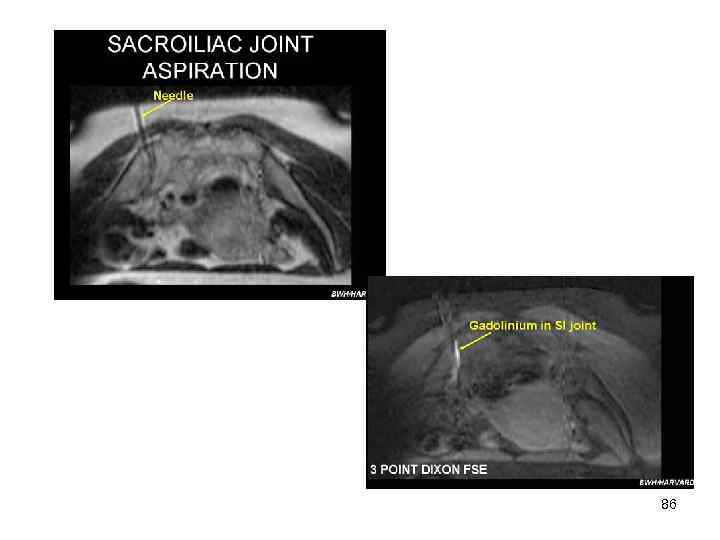

Радикулит Вторичный • Этиология – костный воспалительный процесс • Спондилоартрит (болезни Бехтерева): – • кифоз грудного отдела позвоночника Сакроилеит: – – болезненность при сдавлении крыльев подвздошной кости нечеткость контуров суставных поверхностей крестцовоподвздошного сочленения 84

86